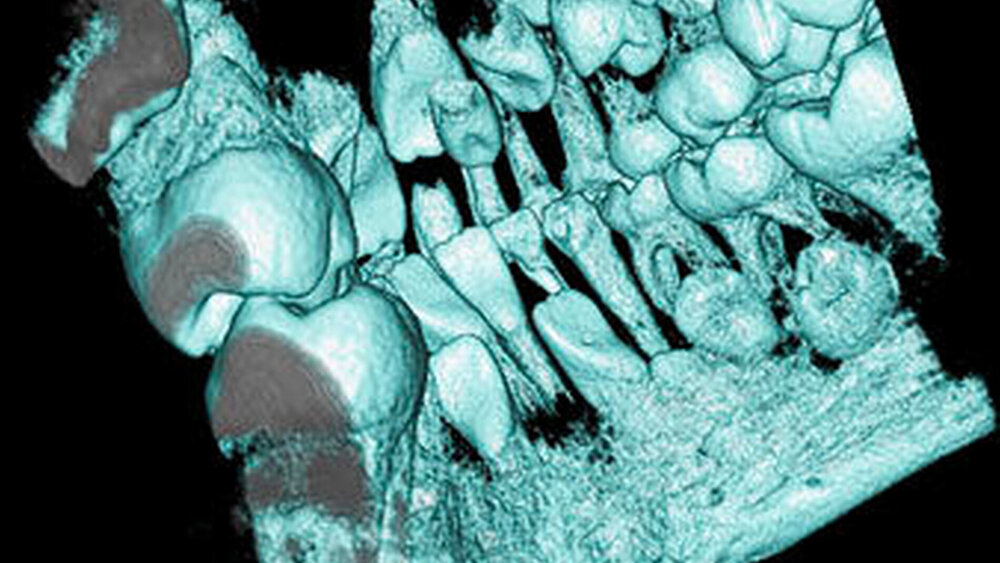

Überzählige Zähne können einzeln oder multipel auftreten [von Arx, 1990; Rajab Hamdan, 2002; Fernández Montenegro et al., 2006; Liu et al., 2007; Gündüz et al., 2008; Ferrés-Padró et al., 2009; Hyun et al., 2009]. Einzelne überzählige Zähne treten in 65,8 bis 80,5 Prozent, doppelte in 14,5 bis 27,7 Prozent und multiple in 0,6 bis 8 Prozent der Fälle auf [Rajab Hamdan, 2002; Fernández Montenegro et al., 2006; Liu et al., 2007; Ferrés-Padró et al., 2009; Hyun et al, 2009; Mossaz et al., 2014]. Einzelne oder doppelte überzählige Zähne finden sich typischerweise in der Oberkieferfront [Rajab Hamdan, 2002; Fernández Montenegroet al., 2006; Mossaz et al., 2014]. Multiple überzählige Zähne werden vor allem im Prämolarenbereich des Unterkiefers gefunden [Abbildung 4; YUSOF 1990, Ferrés-Padróet al., 2009; Wang Fan, 2011]. Multiple überzählige Zähne sind zudem oft mit anderen Erkrankungen oder Syndromen assoziiert, dazu gehören Lippen-Kiefer-Gaumenspalten, die cleidokraniale Dysplasie oder auch das Gardner-Syndrom. Bei Patienten mit einer Lippen-Kiefer-Gaumenspalte wird vermutet, dass sich die überzähligen Zähne aus der Fragmentierung der dentalen Lamina bei der Spaltbildung ergeben [Garvey et al., 1999; Wang Fan, 2011].